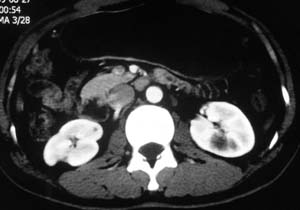

以下是引用子期在2010-3-19 20:47:00的发言:[br]血管畸形的ct增强应该有明显强化,本例并不相符合。本例双肾局部的略低密度影,累及肾盂,局部皮质明显变薄、内陷,增强扫描有轻度的强化,应考虑为炎性病变,患者为年轻男性,累及双肾的感染以结核较常见,可以没有明显的临床症状,尿中有时候也并不能查出什么;肾脓肿常有明显感染中毒症状,本例不符,另外一般的肾盂肾炎或肾小球肾炎通过小便就可确诊,其它还不能排除的是黄色肉芽肿性肾盂肾炎,然而单凭ct一般也很难鉴别。